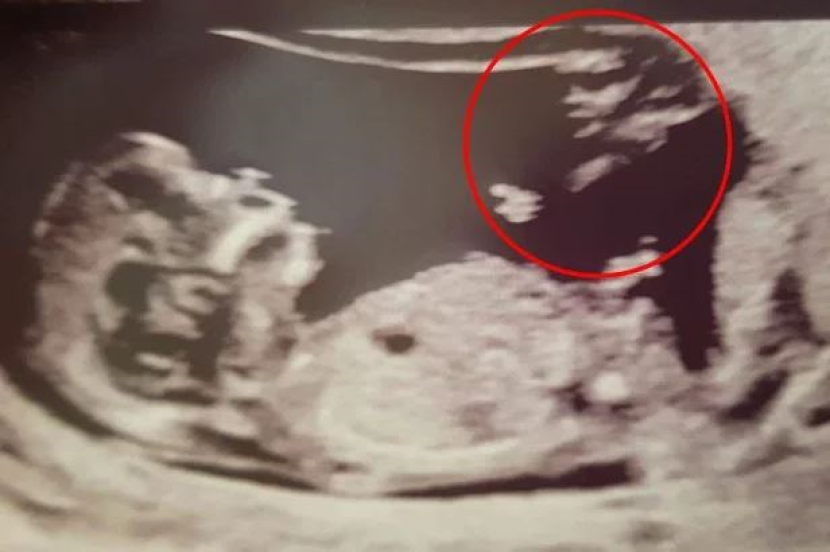

Setelah berjaya hamil, mereka ada membuat imbasan bayi sebelum dikejutkan dengan satu wajah misteri.

"Saya hantar gambar itu kepada ibu dan emak saudara kerana rasa ada sesuatu yang pelik.

"Mereka berdua pun nampak ada wajah lain," ujar Britainy.